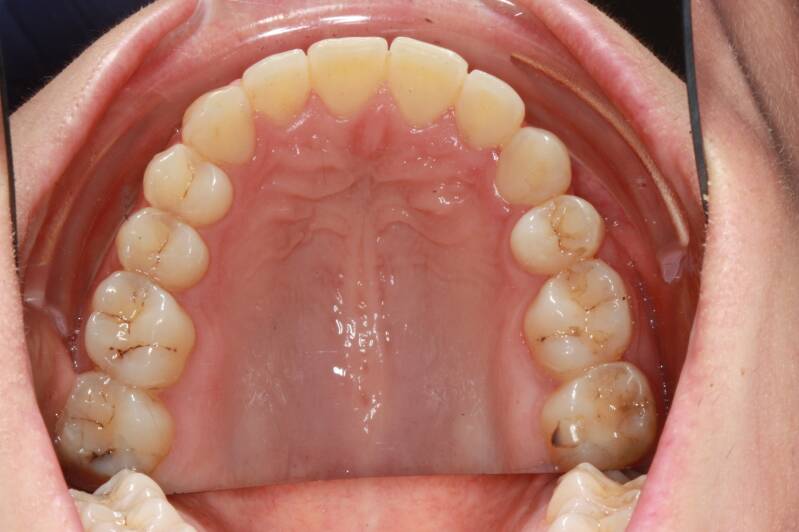

FOTO INIZIALI PRE TRATTAMENTO ORTODONTICO

PRIMA CLASSE CON AFFOLLAMENTO GRAVE SUPERIORE A SINISTRA CON PERDITA PRECOCE DEL SECONDO MOLARE INFERIORE SINISTRO

Abbiamo appena portato a termine questo caso che presentava in arcata superiore il primo premolare di sinistra completamente fuori arcata sovrapposto al secondo premolare ed il canino ruotato.